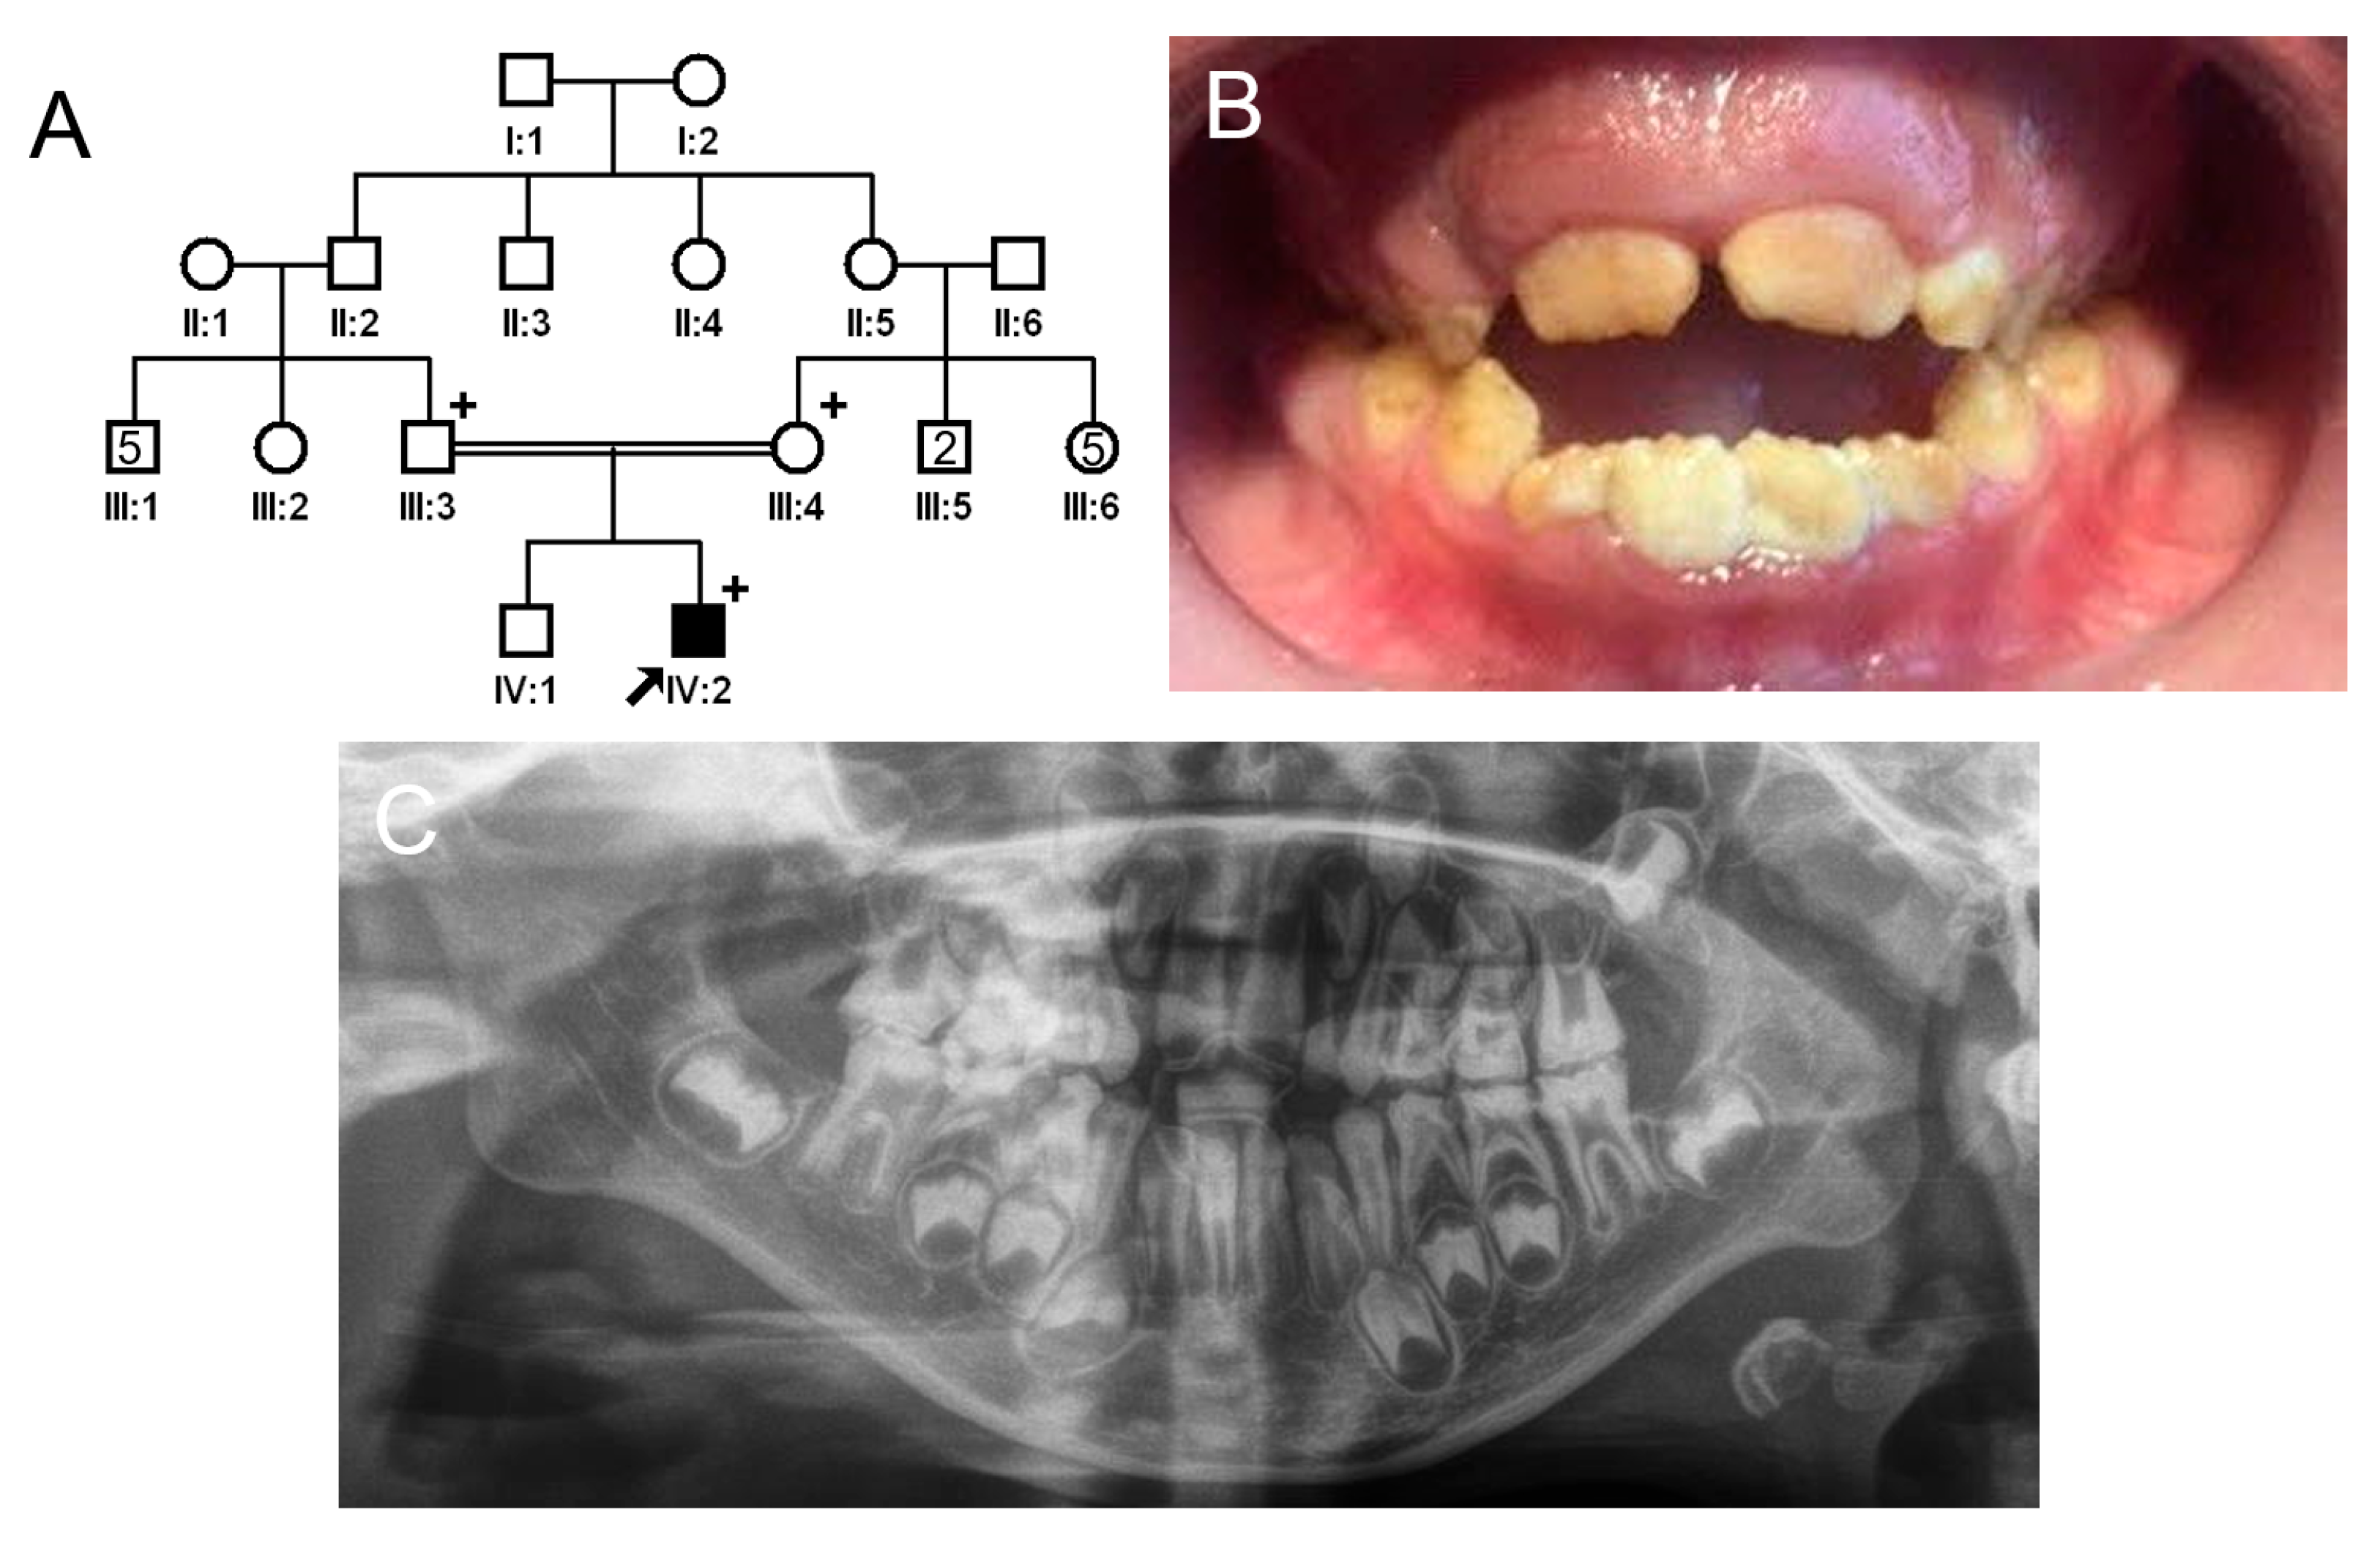

3.2. Family 2

The proband of family 2 was a 7-year-old male, the second child from a consanguineous Turkish family (Figure 3). He had no other remarkable past medical history. His newly erupted permanent anterior teeth exhibited brown discoloration but a normal shape because the hypomineralized enamel had not yet fractured. However, the remaining deciduous teeth and first permanent molars exhibited apparent attrition and enamel fractures. There were no other affected family members except for the proband; therefore, a recessive or de novo mutation was suspected.

Figure 3.

Pedigree, clinical photo, and panoramic radiograph of family 2. (A) Pedigree of family 2. The black symbol indicates the affected individual, and the proband is indicated by a black arrow. A plus sign above the symbol indicates participating individuals. (B) Clinical photo of the proband at age 7 years. He has an anterior open bite with a constricted maxilla. (C) Panoramic radiograph of the proband at age 7 shows enamel fractures and attrition in almost all posterior teeth including first molars. The affected enamel has reduced radiopacity, making it similar to the underlying dentin.